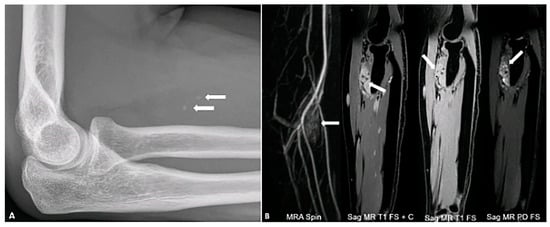

4.8. Tumors of Uncertain Differentiation

- Murphey, M.D.; Gibson, M.S.; Jennings, B.T.; Crespo-Rodríguez, A.M.; Fanburg-Smith, J.; Gajewski, D.A. Imaging of synovial sarcoma with radiologic-pathologic correlation. Radiographics 2006, 26, 1543–1565. [Google Scholar] [CrossRef] [PubMed]

- Wilkerson, B.W.; Crim, J.R.; Hung, M.; Layfield, L.J. Characterization of synovial sarcoma calcification. Am. J. Roentgenol. 2012, 199, W730–W734. [Google Scholar] [CrossRef] [PubMed]

- Chotel, F.; Unnithan, A.; Chandrasekar, C.; Parot, R.; Jeys, L.; Grimer, R. Variability in the presentation of synovial sarcoma in children: A plea for greater awareness. J. Bone Jt. Surg. Br. Vol. 2008, 90, 1090–1096. [Google Scholar]

- Liang, C.; Mao, H.; Tan, J.; Ji, Y.; Sun, F.; Dou, W.; Wang, H.; Wang, H.; Gao, J. Synovial sarcoma: Magnetic resonance and computed tomography imaging features and differential diagnostic considerations. Oncol. Lett. 2015, 9, 661–666. [Google Scholar]